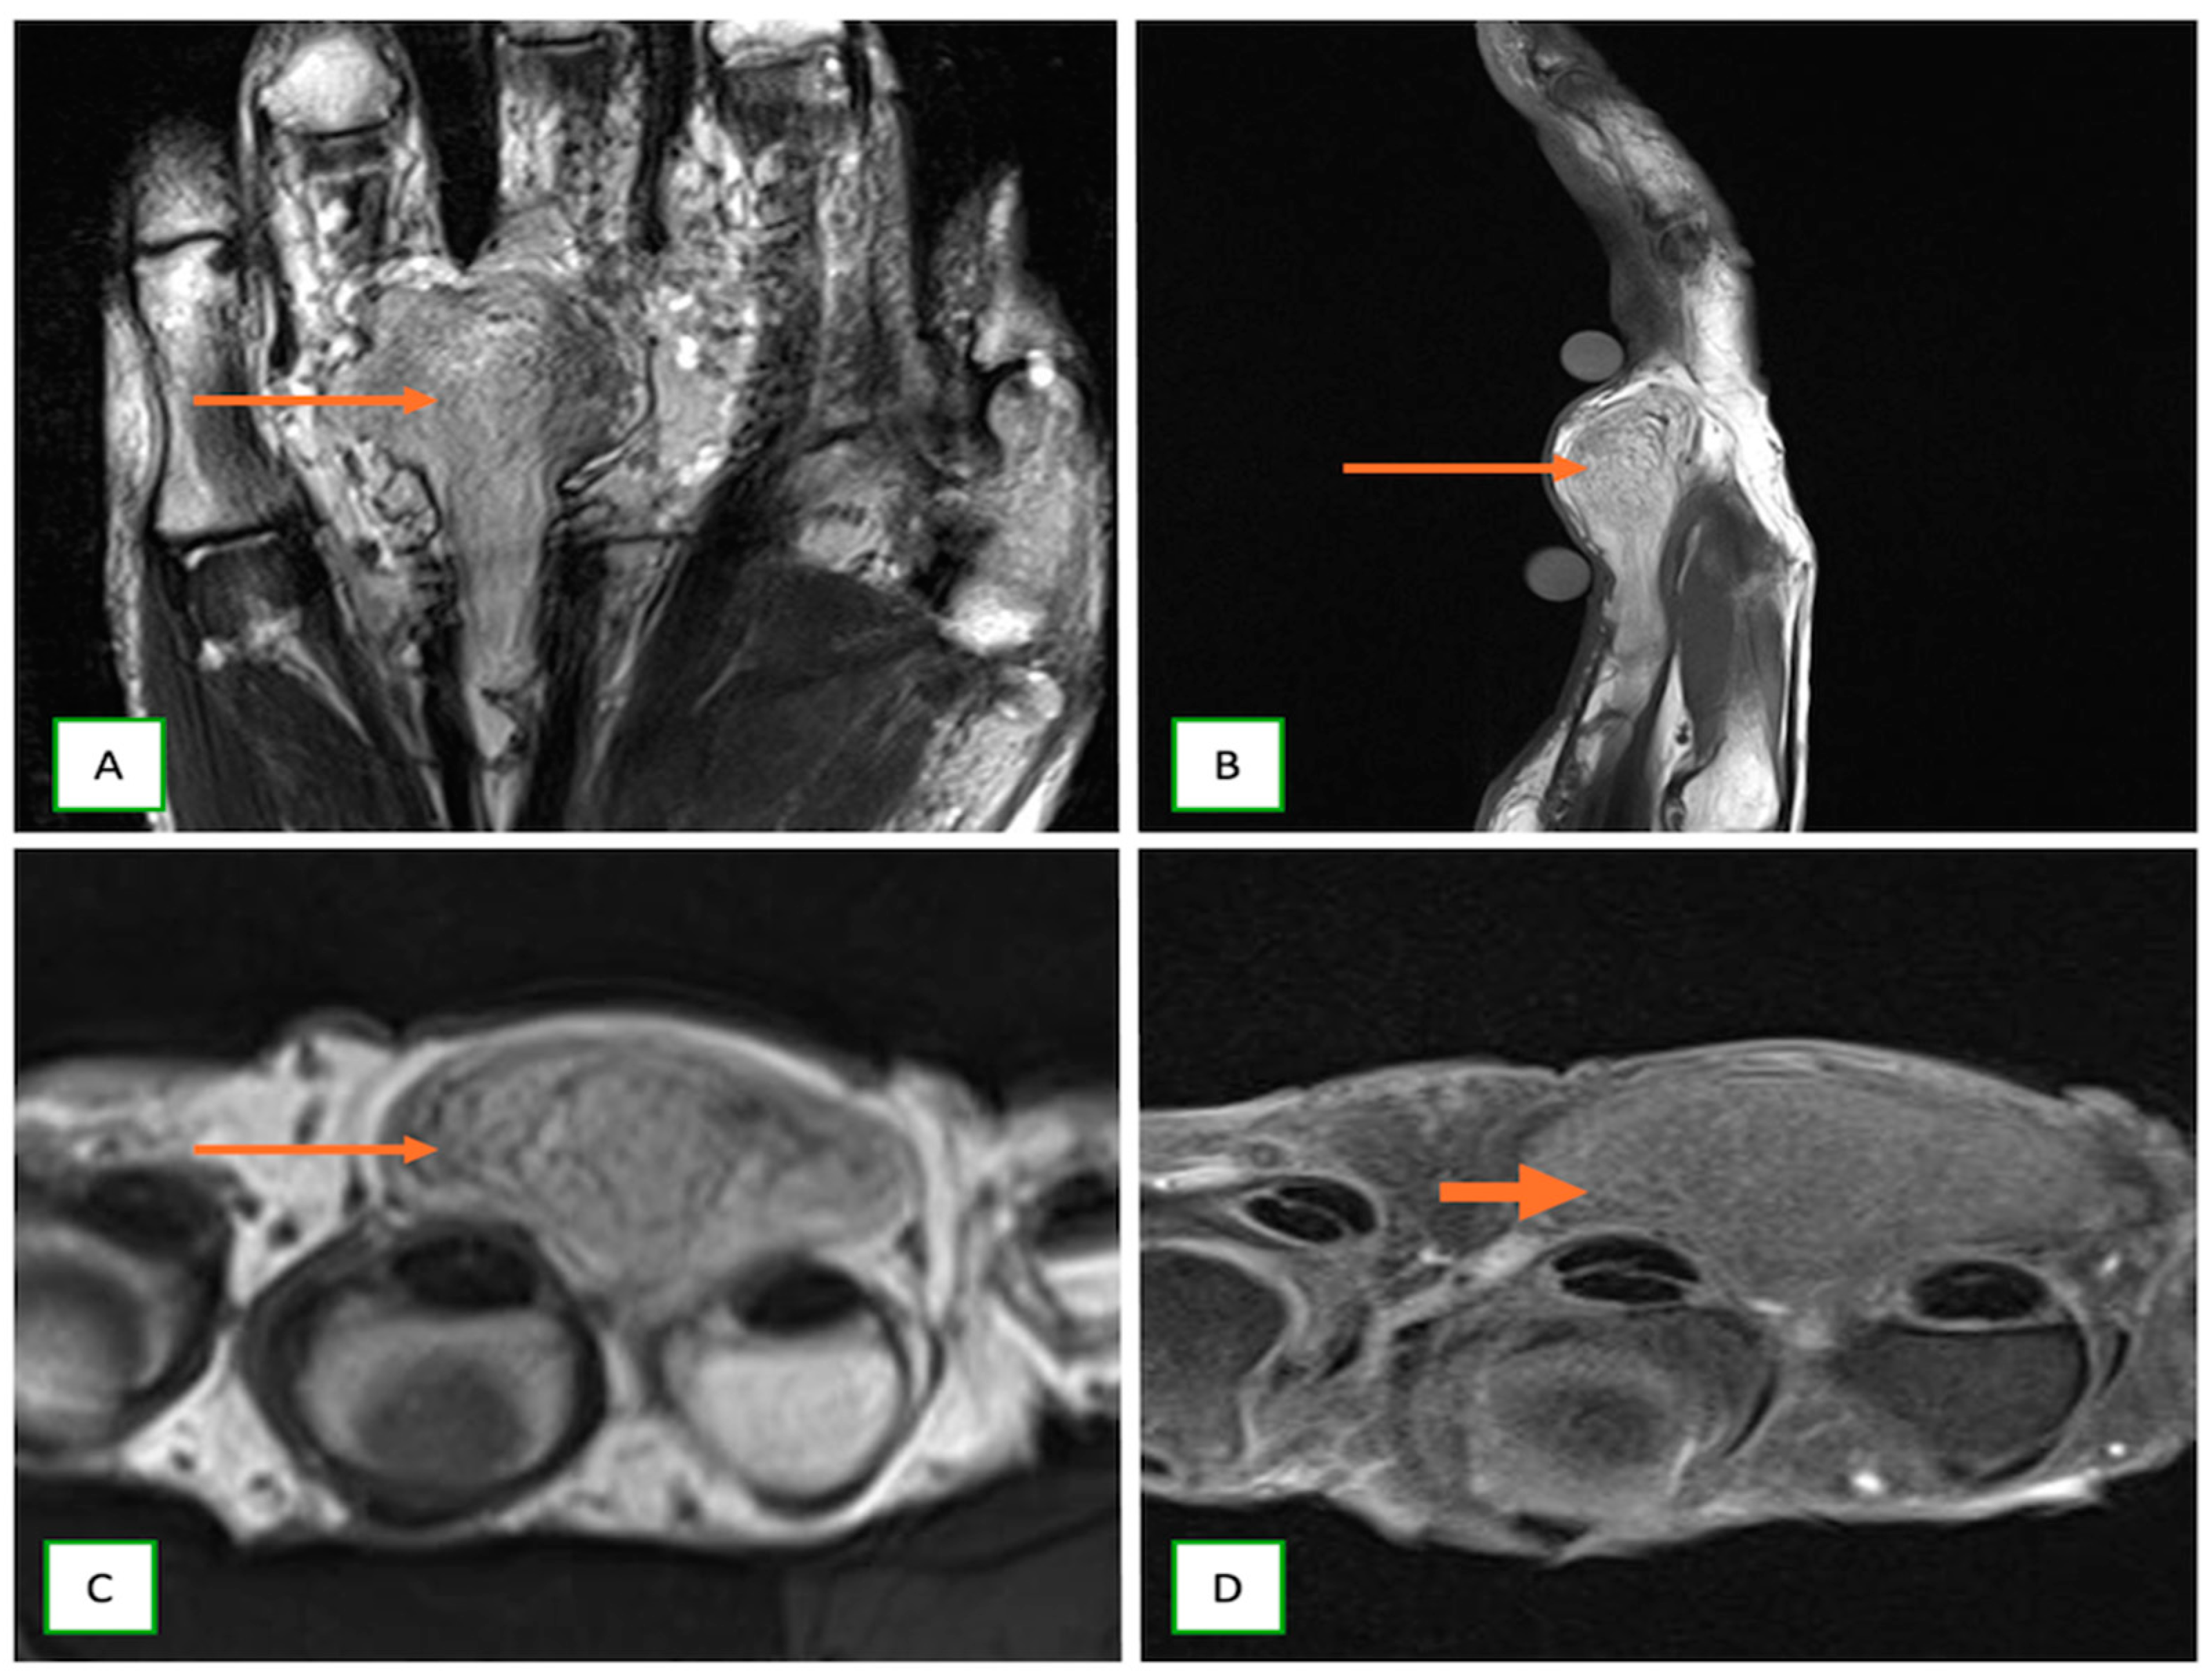

- Primary Sarcomas: Soft-tissue sarcomas are uncommon, accounting for just over 1% of adult malignancies. Synovial sarcoma, clear cell sarcoma, and epithelioid sarcomas are known to involve peripheral nerves. CT/MR reveals a large soft tissue mass with areas of necrosis or calcification and heterogeneous contrast enhancement. F-18 FDG uptake is useful for both tumor staging and treatment assessment (Figure 26, Figure 27 and Figure 28).